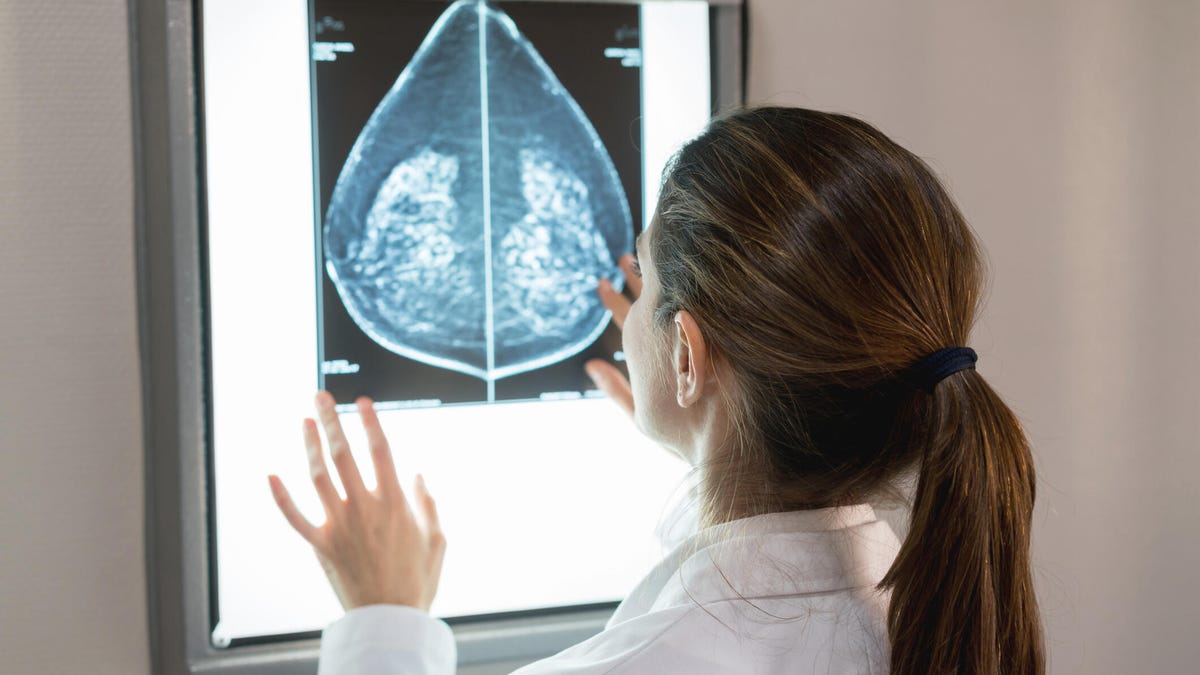

From now on, your doctor will tell you if your breast tissue is either "dense" or "not dense" after a mammogram or mammography, which provides an x-ray picture of the breast. But what does this mean? We talked to two doctors about how breast density is measured, whether it increases your risk of breast cancer and why it may change over your lifetime.Â

Breast density refers to the way your breast tissue looks on a mammogram. Dense tissue is difficult to see through on the mammogram, while less dense tissue is more transparent. Many people have dense breast tissue (about 4 out of 10 women have heterogeneously dense breast tissue), and if your doctor tells you you're among them, it doesn't mean anything is wrong.Â

We asked Dr. Michelle Townsend-Day, chief of breast imaging for MedStar Union Memorial and MedStar Good Samaritan Hospitals in Baltimore, Maryland, what this means for interpreting mammograms. She explained that practitioners who assess mammogram results are looking at both "fatty tissue, which is black on mammograms, and fibroglandular tissue, which is white on mammograms."

Fibroglandular tissue appears white on a mammogram because it is more dense than fatty tissue.

How much of your tissue must be white on the mammogram before it's considered dense? Dr. Townsend-Day says, "Dense breast tissue means that the breast is made up of 50% to 100% fibroglandular tissue."

If your breast tissue is dense, it may be easier for a radiologist to miss an abnormality. That being said, there is no need for immediate alarm. Breast tissue can be both dense and completely healthy.Â

As Dr. Cabeca reminds us, "It is harder to read a mammogram on breasts that have dense tissue because they appear white on the images. That makes the regular tissue harder to discern from potential masses, which also appear in white." Because of this common issue, the doctor says that people "with dense breast tissue may get called back for additional tests more often."